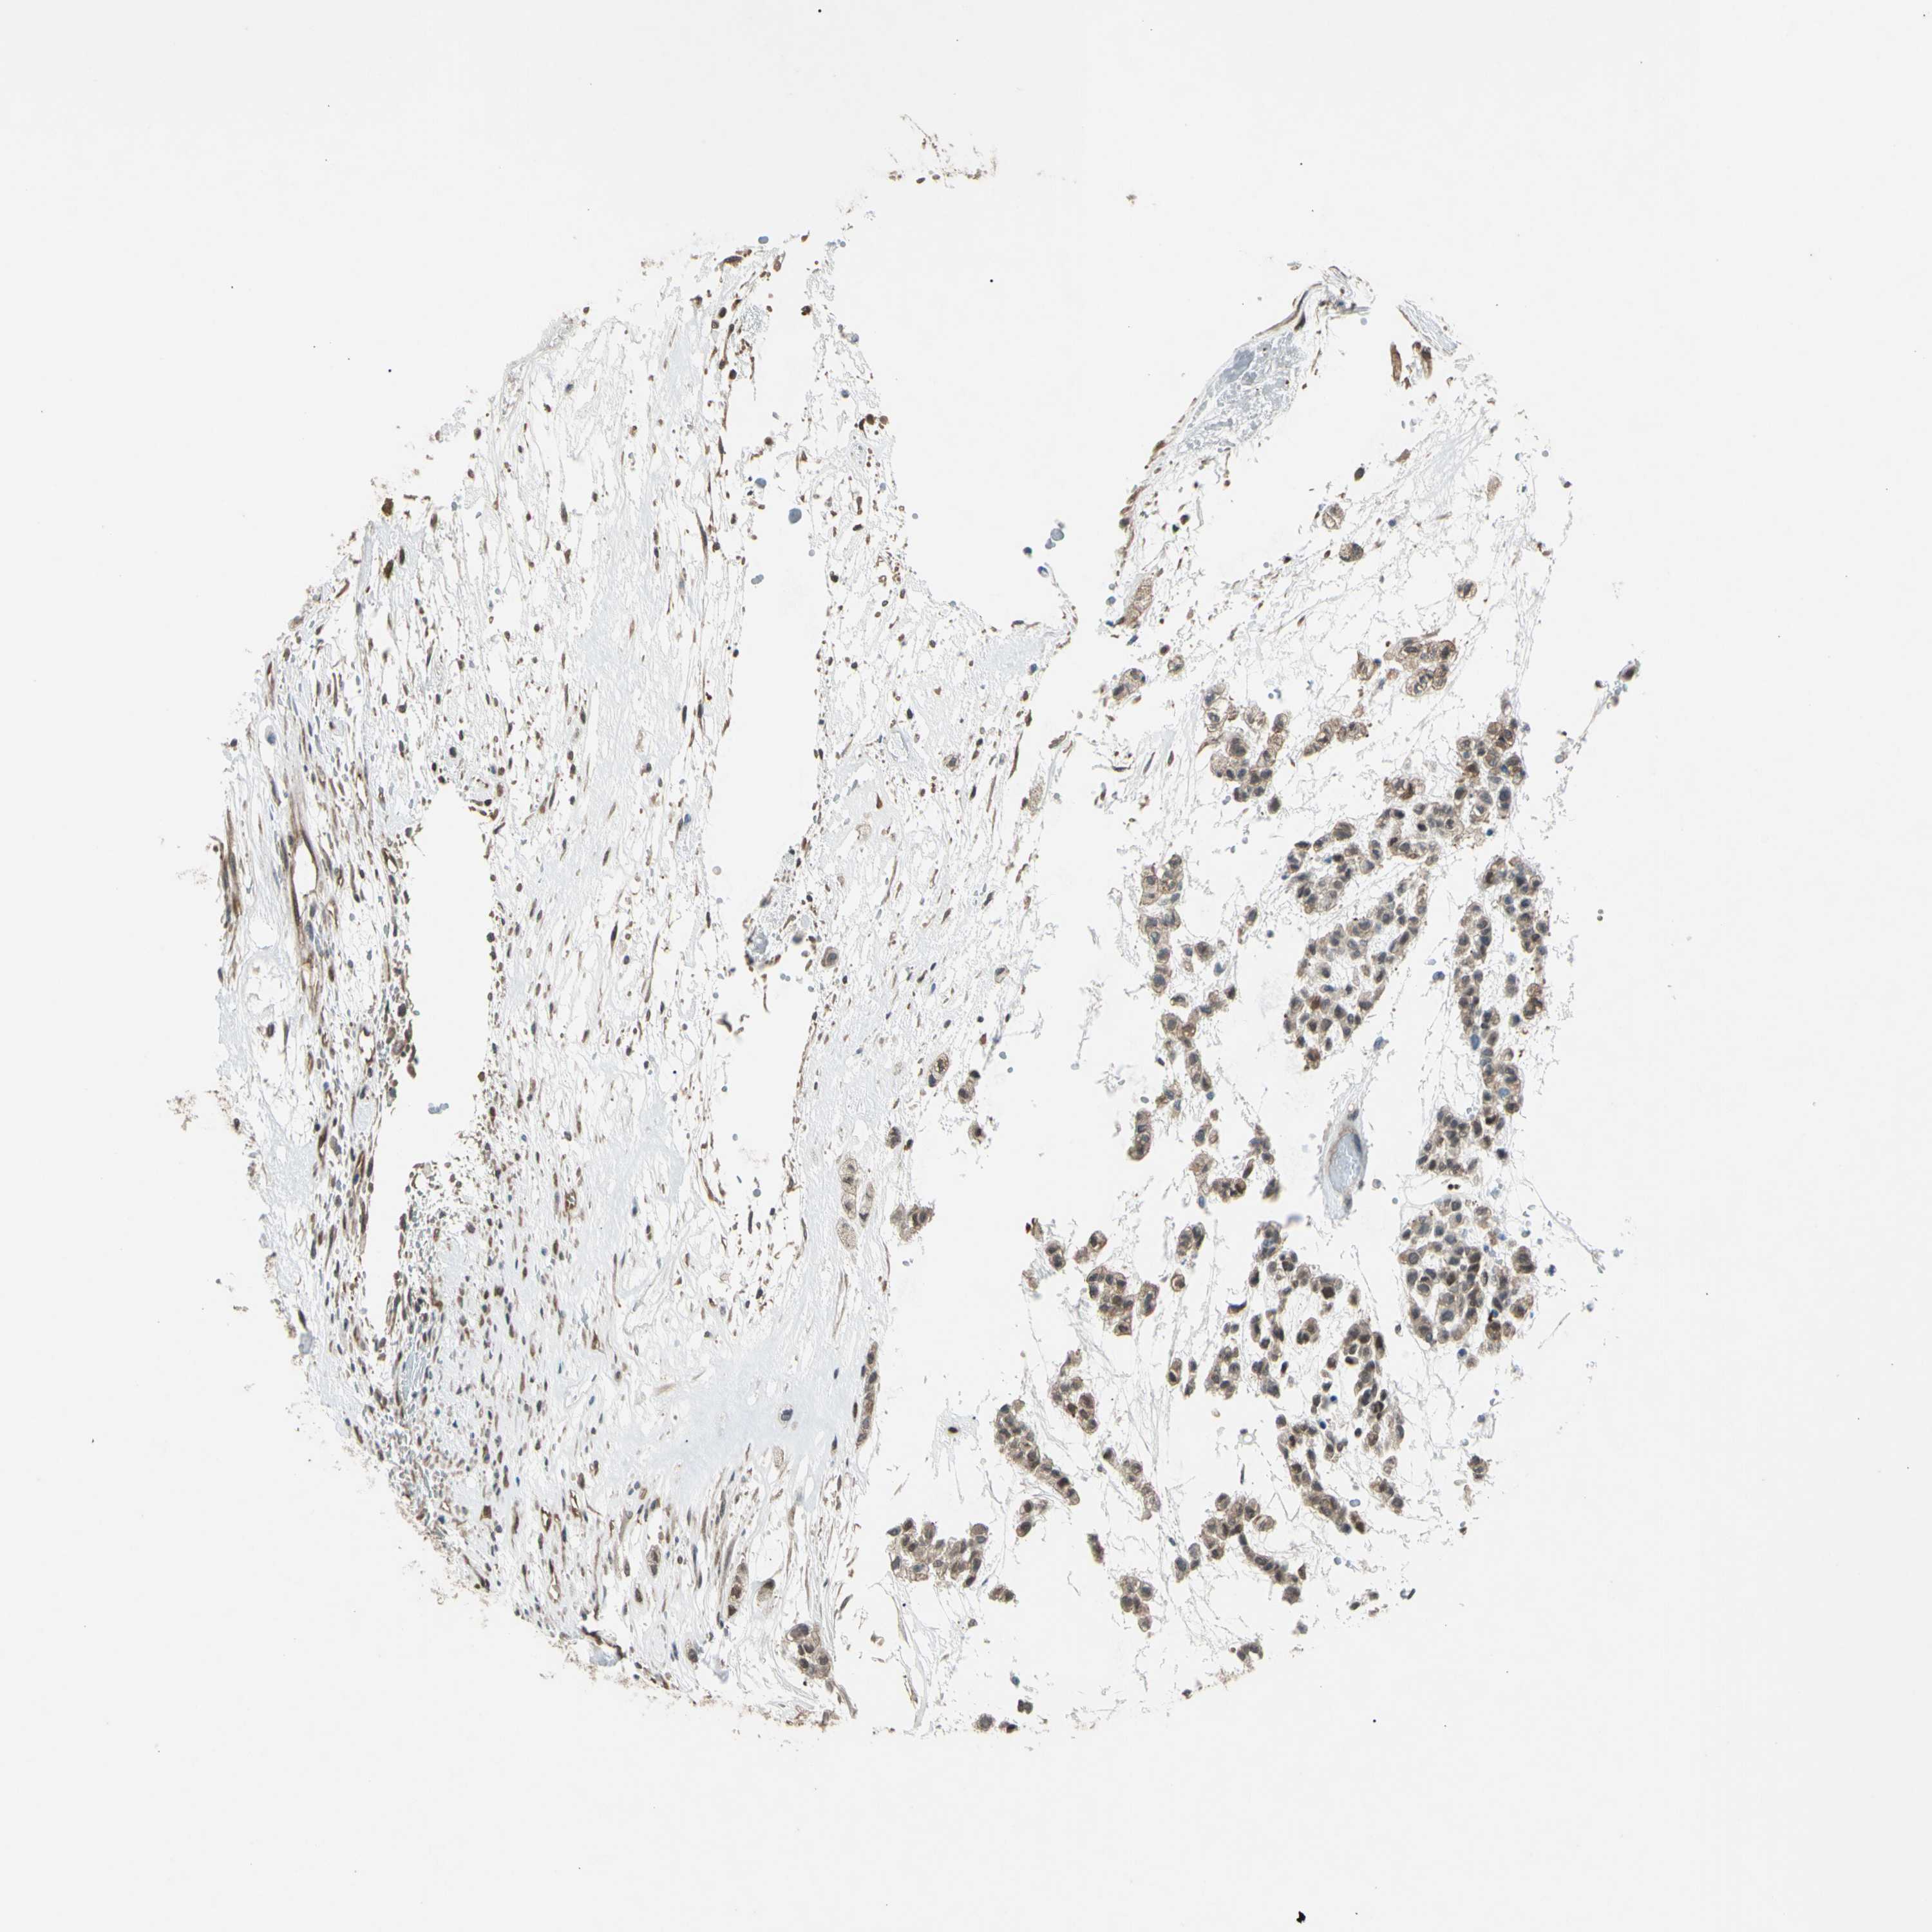

HEAD AND NECK CANCER - Protein expressioni

A mouse-over function shows sample information and annotation data. Click on an image to view it in a full screen mode. Samples can be filtered based on level of antibody staining by selecting one or several of the following categories: high, medium, low and not detected. The assay and annotation is described here.

Antibody stainingi

Antibody staining in the annotated cell types in the current human tissue is reported as not detected, low, medium, or high, based on conventional immunohistochemistry profiling in selected tissues. This score is based on the combination of the staining intensity and fraction of stained cells.

Each image is clickable and will lead to virtual microscopy that enables deeper exploration of all samples and also displays staining intensity scores, fraction scores and subcellular localization as well as patient and tissue information for each sample.

Antibody HPA007925

Antibody CAB010286

Staining

High

Medium

Low

Not detected

Intensity

Strong

Moderate

Weak

Negative

Quantity

>75%

75%-25%

<25%

None

Location

Nuclear

Cytoplasmic/membranous

Cytoplasmic/membranous,nuclear

Squamous cell carcinoma, NOS

Adenocarcinoma, NOS

Adenoma, NOS

Squamous cell carcinoma, metastatic, NOS